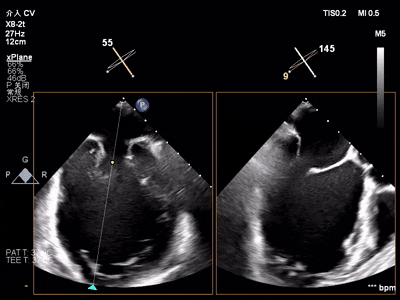

术前术后反流对比

【术后一周复查心超提示】二尖瓣钳夹术后,二尖瓣反流(轻度),夹合器固定,瓣口呈双孔结构,内外侧孔分别见微量反流,反流束VC分别 0.15cm、0.18cm,估测有效瓣口面积约2.5c㎡,舒张期瓣口前向最大血流速度 1.2m/s,平均压差3mmHg,左室射血分数(EF)值提升至35%,心功能显著改善。目前患者已顺利康复出院。